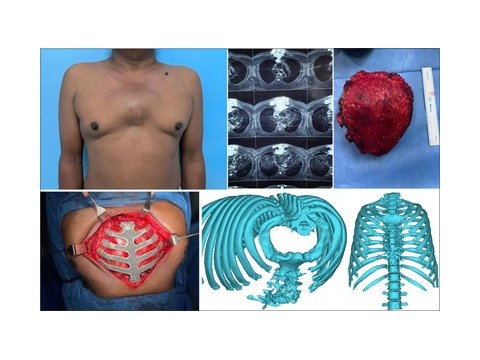

- 3D打印实现手术“私人定制”

- 长沙市中医院应用3D打印技术制作百余例模型,助力精准医疗

- 烟台山医院完成3D打印辅助截骨矫形治疗儿童肘内翻畸形手术

- 印度医院3D打印钛合金胸骨植入物,拯救了癌症患者的生命

- 3D扫描+3D打印技术,开启骨科微创精准矫正手术“私人定制”时代